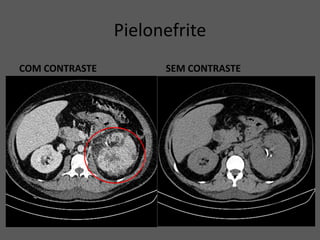

Pielonefrite

COM CONTRASTE SEM CONTRASTE